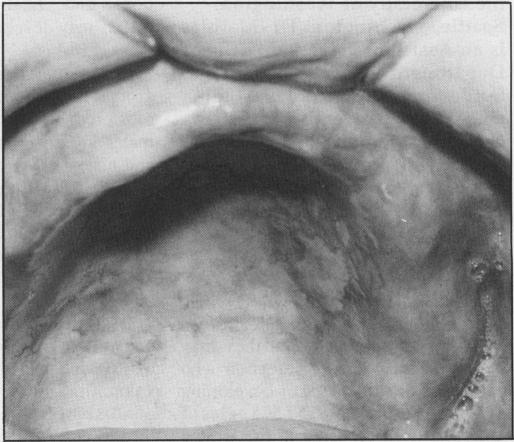

The AIDS epidemic continues. All health-care workers, including physicians and dental personnel, may be instrumental in recognizing risk factors associated with Acquired Immunodeficiency Syndrome (AIDS) and Human Immunodeficiency Virus (HIV) infection. Oral signs and symptoms of HIV infection may be the first presentation of the disease or may develop during the course of the disease and require management. Knowledge of the signs, symptoms and associated infections and tumours is needed to assist in recognition, diagnosis, and treatment.